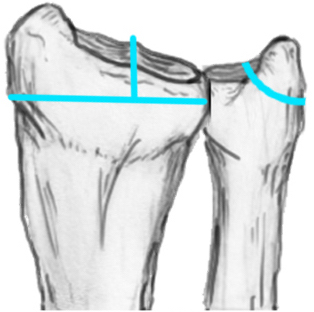

Unacceptable reduction

1. Distal radial Step > 2mm

2. Articular incongruency sigmoid notch / DRUJ > 2 mm

3. Radial shortening > 5 mm

4. Radial inclination < 15o

5. Sagittal tilt

- > 15o dorsal

- > 20o volar